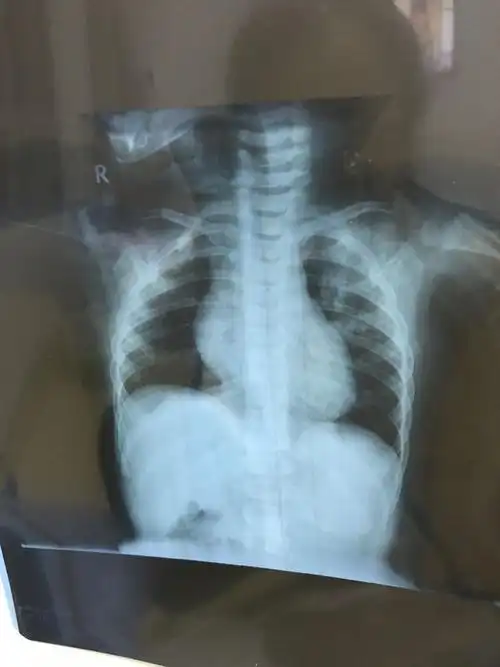

宝宝一岁支气管肺炎